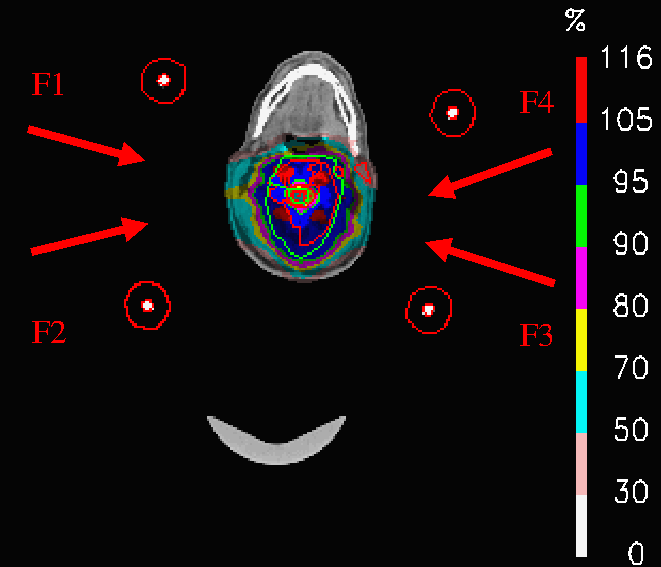

The strategy followed in the nominal treatment (PLAN-NOM) was to draw safety volumes around the metallic rods and to apply hard dose constraint to such volumes of interest (VOIs), as shown in Fig.2, such that the pencil beams of the four fields (F1, F2, F3, F4) involved in the treatment were safe from hitting the rods.

Figure 2: Patient with metallic cage: nominal IMPT dose distribution; inside the patient volume, the green contour corresponds to the PTV and the red ones to the OARs; otuside the patient volume, the safety VOIs and the effective countours of the 4 metallic rods are visible; the fields F1, F2, F3, F4 used for PLAN-NOM and PLAN-OL-1 are also shown.